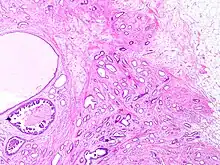

Tubular carcinomas are generally around 1 cm. or smaller, and are made up of tubules. They are usually low-grade.[2] Elastosis has been noted as common but is not present in all cases.[11]

- Image by Mikael Häggström, MD. Reference for typical features: Pragya Virendrakumar Jain, M.D., Julie M. Jorns, M.D. "Breast - Other invasive carcinoma subtypes, WHO classified - Tubular". Pathology Outlines.

A highly differentiated invasive carcinoma that forms well-defined tubules (containing epithelium, but no myoepithelium) and that have abundant desmoplastic fibrous stromal reaction between the tubules.